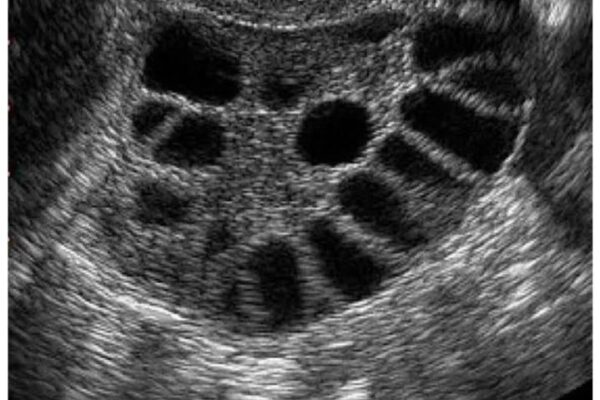

Ташхиси дақиқ ва технологияҳои муосир Таҳлили нутфа, ташхиси гормоналӣ, ултрасадо ва ҷарроҳии гинекологӣ дар як марказ мутамарказ шудаанд.